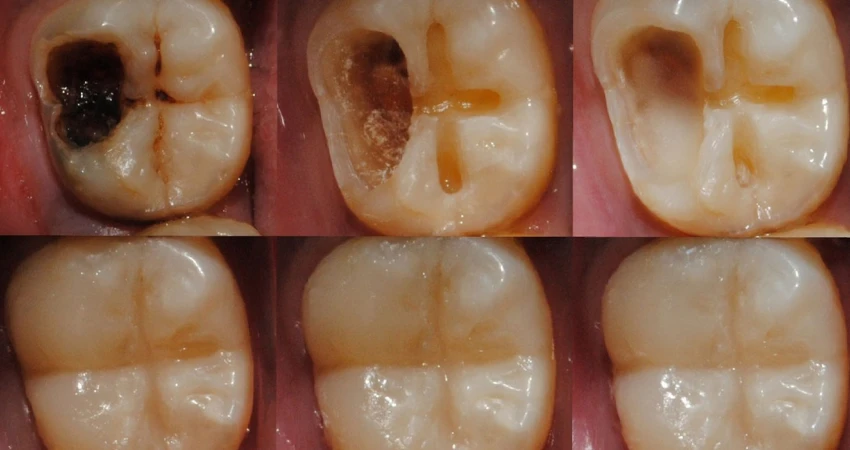

Treating deep tooth decay differs from managing superficial cavities, as it requires more precise intervention to preserve the tooth and prevent its loss.

The dentist typically begins by removing the decayed portion of the tooth using specialized instruments, then thoroughly cleaning the cavity to eliminate bacteria and food debris responsible for pain and inflammation.

The tooth is then restored with a suitable filling material—either tooth-colored (composite resin) or metallic—to rebuild its normal structure and reinforce its walls. If the decay has reached the dental pulp (tooth nerve), root canal treatment is required, which involves cleaning and disinfecting the root canals and then sealing them tightly.

In many advanced cases of deep decay, the dentist may recommend placing a dental crown over the affected tooth to protect it from fracture and to restore its appearance and function.

Early intervention and proper treatment play a crucial role in saving the tooth, relieving pain, and preventing complications such as dental abscesses and gingival inflammation. For this reason, it is advisable to see a dentist promptly if you experience marked sensitivity or deep, persistent pain in a molar.